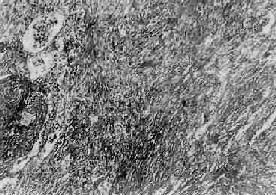

图9-23 矽肺

肺组织呈弥漫性纤维化